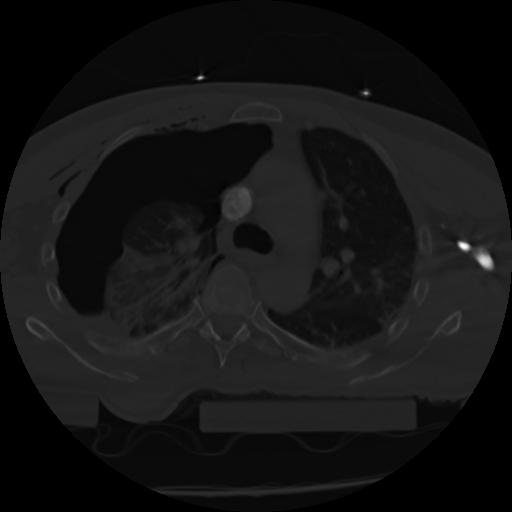

21 ANGIO,CE,Axial,3.0,ANGIO,,